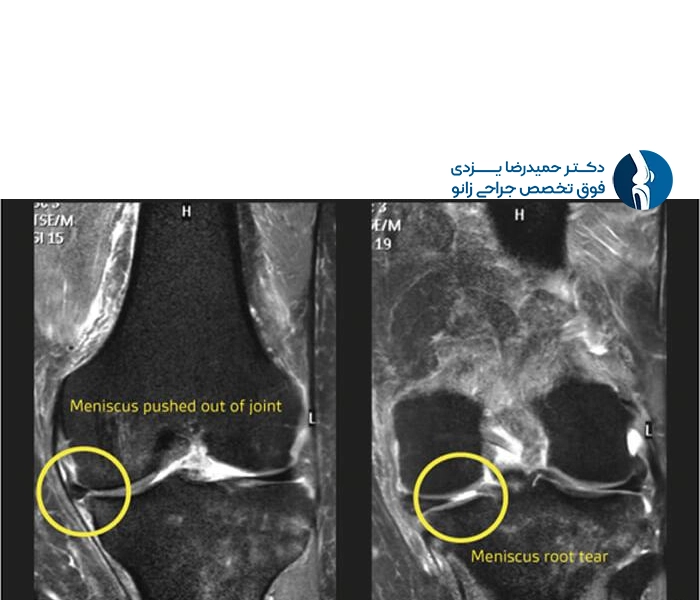

زمان اسکن معمولاً حدود ۲۰ تا ۳۰ دقیقه طول میکشد و طی آن تصاویر دقیق مقطعی از مفصل زانو گرفته میشود. پزشک رادیولوژیست سپس با بررسی این تصاویر، وجود، نوع (افقی، عمودی، طولی)، محل (شاخ قدامی یا خلفی) و شدت پارگی مینیسک را مشخص میکند.

تصویر MRI پارگی مینیسک زانو